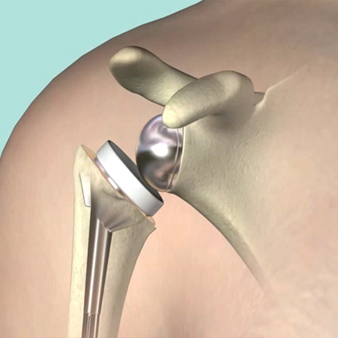

Shoulder Replacement

Shoulder replacement surgery otherwise shoulder arthroplasty, is a surgery involving the replacement of the damaged upper end of the arm bone humerus ( ball) and the shoulder bone socket namely glenoid (socket) with a prosthesis. This method is usually recommended for patients suffering from severe shoulder arthritis whose joint functionality is restricted due to acute pain.